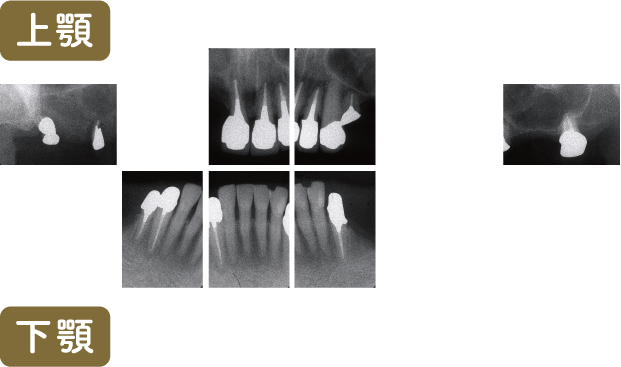

■術前レントゲン写真

左下4,5番の歯は根管治療をおこなう必要がありますが、すでに動揺がみられることと義歯を支える歯という点から、積極的な介入は行わず義歯を再製するのみという治療方針となりました

動揺はありますが、このスイングロックアタッチメントを使用することにより動揺歯が二次固定されて動きが少なくなります

上顎は総義歯のため、下顎のみのレントゲン写真です

レントゲン写真では左右が逆になります